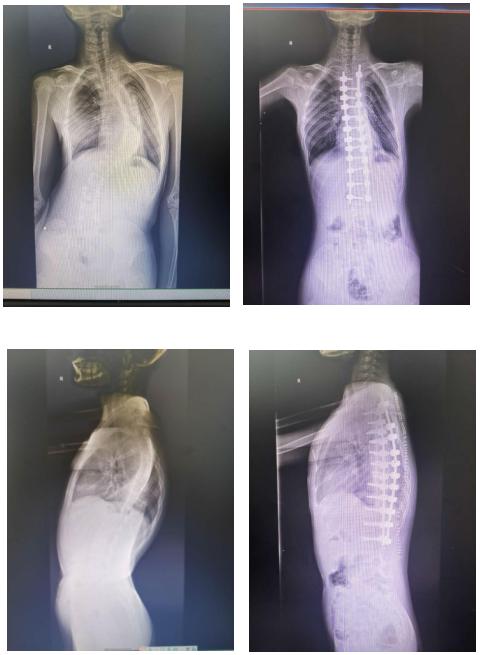

脊柱侧弯患儿脊柱正侧位x线检查术前术后对比

脊柱侧弯治疗前/后对比

术前术后对比

(治疗前后对比图)五,医生治疗感悟治疗脊柱侧弯的时候,一定要分清楚